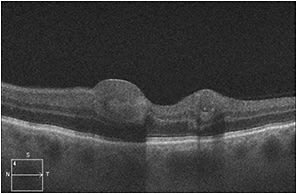

Fluorescein angiography demonstrated numerous punctate areas of hypofluorescence, consistent with blockage from the intraretinal hemorrhages (Figure 2). Spectral-domain OCT scans of the macula showed lesions within the inner retina corresponding to intraretinal hemorrhages but an otherwise unremarkable outer retina with an intact inner segment/outer segment junction and retinal pigment epithelium layer (Figure 3).

Figure 3. At presentation, SD-OCT of the left eye showed lesions corresponding to the intraretinal hemorrhage with shadowing but an otherwise intact outer retina and RPE.

We performed the appropriate baseline tests, including FA and SD-OCT, to rule out any other vision-threatening conditions. As demonstrated in the images, our patient’s retinal hemorrhages improved with observation (Figure 4, page 71). At three months, the patient’s best-corrected visual acuity was 20/25 with almost complete resolution of hemorrhage on fundus examination (Figure 5) and SD-OCT (Figure 6).

Figure 6. At three months, SD-OCT of the left eye showed complete resolution of the subfoveal intraretinal hemorrhage.